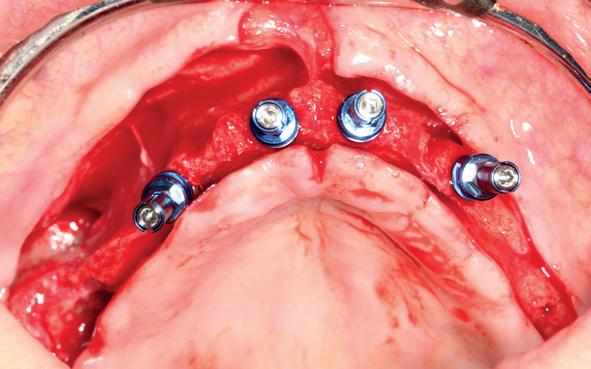

5. Implantaten geplaatst op geleide van een boorsjabloon; botopbouw met sinuslift volgens de GBR-techniek en Caldwell Luc methode; materialen: Oragraft & BioOss, Ossix membr, hyaluronzuur. In de BK is gekozen voor Bego implantaten (Bego SC en RSX 3,75x 11,5 & 13mm).

6. In het front zijn Bego 3,25mm

Tijdens de chirurgische behandeling worden na het afschuiven van de flap de posities bepaald van de implantaten met de boorsjabloon. In de bovenkaak worden 7 implantaten geplaatst en in de onderkaak 8

implantaten geplaatst terwijl in de zijdelingse delen voor een bredere diameter (3,75 & 4,1) is gekozen, met lengte 8,5 en 10mm.

7. OPT na abutmentchirurgie 6 maanden later. De integratie van de implantaten met de botopbouw & sinusliften verloopt voorspoedig.

(zie foto’s chirurgie en OPT’s). Gekozen is voor Bego SC & RSX Pro van een relatief smalle diameter (3,253,75). Alleen in de molaarstreek valt de keuze op een 4,1 mm in diameter. De lengte varieert tussen 8,5 en 13 mm afhankelijk van de ligging van de nervus alveolaris inferior en het foramen mentale als de neusbodem en de sinusholte. De keuze van de diameter wordt mede bepaald door de breedte van de processus ondanks de uit te voeren laterale botopbouw. Indien mogelijk gaat de voorkeur uit naar het plaatsen van implantaten in autoloog en daarmee vitaal bot.

Lateraal van de implantaten wordt de kaak fors uitgebouwd volgens de Hybride GBR-techniek met Oragraft (allograft) van Lifenet die wordt vermengd tot een cocktail met BioOss (xenograft) van Geistlich, autoloog geoogste botsnippers en verzameld bloed uit het wondgebied. De botgraft wordt bedekt met een Ossix (crossed linked) membraan en met Hyadent (hyaluronzuur) overspoten. De sinuslift wordt gelijktijdig met de laterale botopbouw volgens de Caldwell Luc methode uitgevoerd en de uitgeprepareerde holte opgevuld met de botgraft. De flaps worden eerst horizontaal ontlast (gemobiliseerd) en vervolgens naar elkaar toe gehecht met vicryl rapide. Daarbij wordt gebruikgemaakt van horizontale matrassen, zodat de wondranden passief tegen elkaar